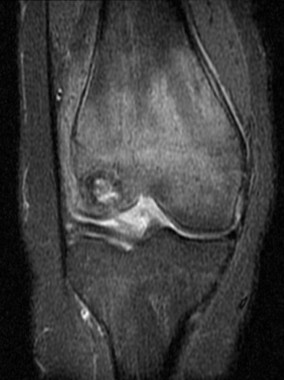

Chondroblastome

Publié 14 juillet 2015 à 766 × 1024 dans Tumeurs os – Chondroblastome

IRM

Case courtesy of Radiopaedia.org. From the case Chondroblastoma